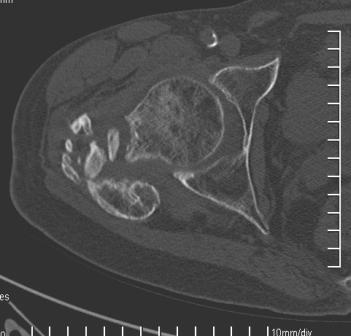

[Ortho] Сросшийся со смещением чрез-подвертельный перелом

Больной Н. 44 года травма 1,5 года назад июнь 2008 года чрез-под вертельный  перелом правого бедра. Во время лечения у больного развился алк делирий,  проводилось консертативное лечение перелома.

На КТ перелом сросся за счет костной мозоли.